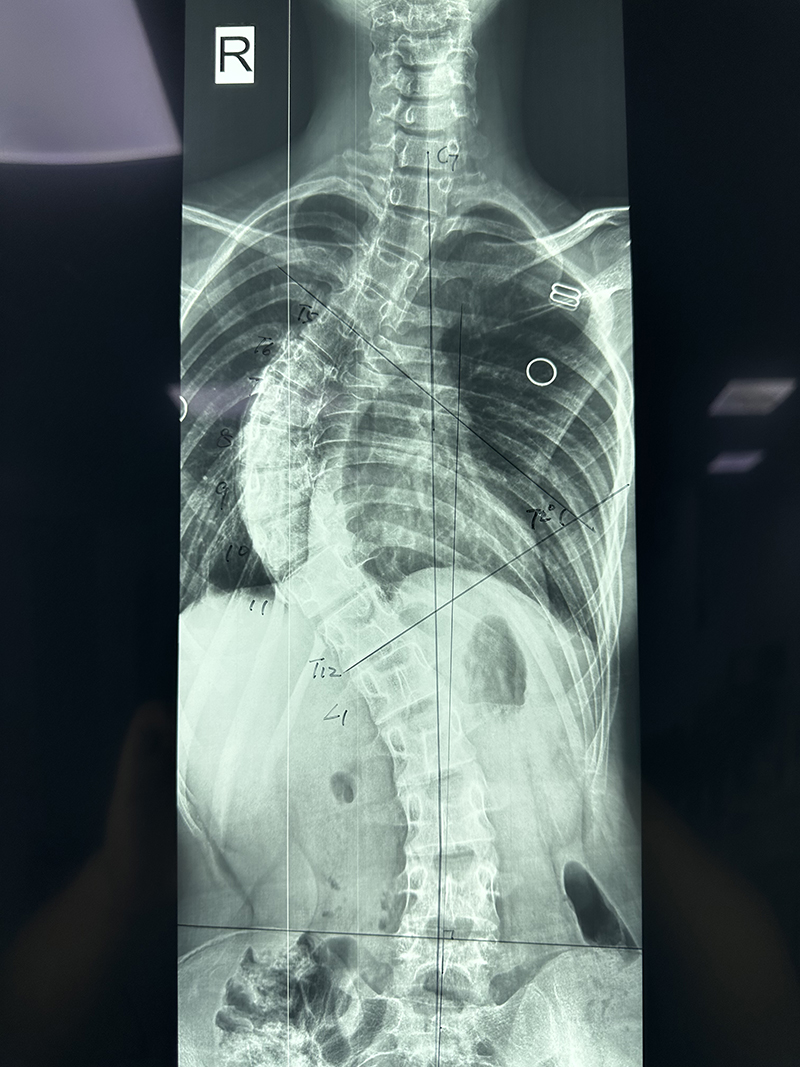

为了解决孩子的“心病”和“身病”,蕾蕾的父母带着她来到柳州市人民医院脊柱外科求助。住院完善相关检查后,医生发现蕾蕾脊柱侧凸畸形严重,双肩明显不等高,右侧肩胛骨明显突出,右侧胸前凹陷,衡量侧凸的Cobb角约72°。

“患者的情况属于青少年特发性脊柱侧弯,检查显示脊柱呈‘S’形侧弯,因为弯曲度数已超过45度,及时进行手术治疗才能最大限度地纠正脊柱侧弯畸形状态,在改善患者外观的同时,避免胸腹腔脏器受到挤压,改善患者的心肺功能!”柳州市人民医院脊柱外科主任胡朝晖说。